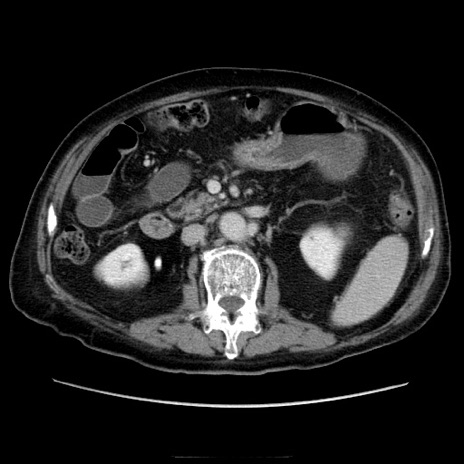

冠状断像

症例21(横断像)

【症例】70歳代男性

【現病歴】肝硬変・肝細胞癌にてかかりつけの方。約9時間前に食後より腹痛出現。症状が徐々に増悪し、嘔吐出現したため来院。

【既往歴】肝硬変、肝細胞癌(RFA、TACE後)